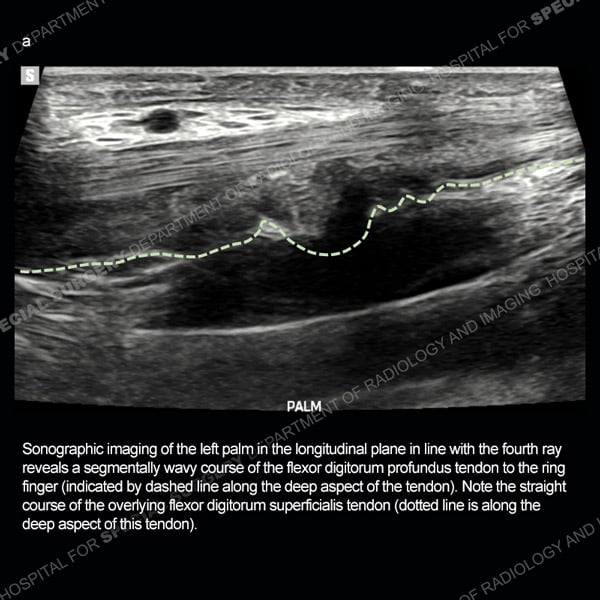

![]() |

Featured Ultrasound of the Month Case |